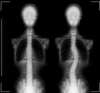

La scoliose, différente de l’attitude scoliotique, est une déviation permanente de la colonne vertébrale due à une rotation des vertèbres. Elle se déclare principalement lors de la croissance, jusqu’à l’adolescence.

On retrouve 2 localisations principales de la scoliose, la scoliose thoracique et la scoliose lombaire. Une scoliose peut également être entre ces deux régions du rachis, on parlera alors d’une scoliose thoraco-lombaire.

La scoliose thoracique se situe donc au niveau de la cage thoracique, entre la 1ère (T1) et la 12ème (T12) vertèbre dorsale. Elle peut déformer la cage thoracique entrainant une déformation de la poitrine, altérant la respiration profonde et peut, dans les cas les plus graves, engendrer une insuffisance pulmonaire.

La scoliose lombaire se situe entre la 1ère (L1) et la 5ème (L5) vertèbre lombaire. Les conséquences principales de cette scoliose est la limitation de l’espace dans l’abdomen pour les organes digestifs, et l’apparition de discopathies (ou hernies discales dans les formes plus avancées) de manière précoce.